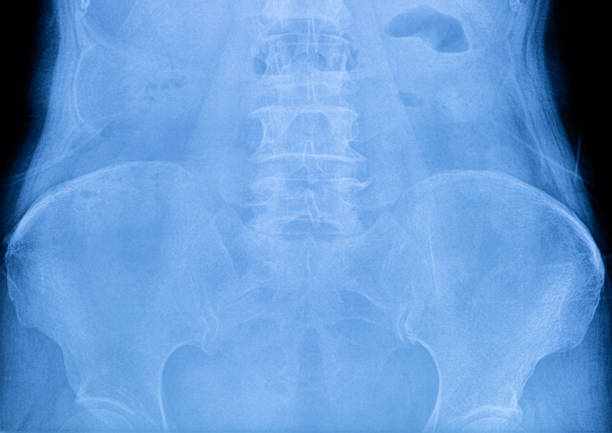

골반은 복부 하단에 위치하고 있는데 양쪽의 2개 볼기뼈와 후단부의 천골(엉치뼈)와 미골(꼬리뼈)로 구성되어 있으며 척추 부분과 하지를 연결하여 체중을 지탱하며 각종 내장과 자궁, 난소, 방광 등 주요 장기를 외부 충격에서 보호할 수 있습니다.

처장관절은 천골(엉치뼈), 장골(엉덩이뼈)가 만나는 부위로 외부 충격 혹은 골반이 힘을 주며 불편한 자세로 일어나거나 한쪽으로 체중이 쏠리는 잘못된 자세로 인하여 천장관절 주변으로 조직이나 인대 등에서 통증을 유발하는데 심할 경우 계단 오르내리는 것 자체도 어려워 질 수 있습니다.